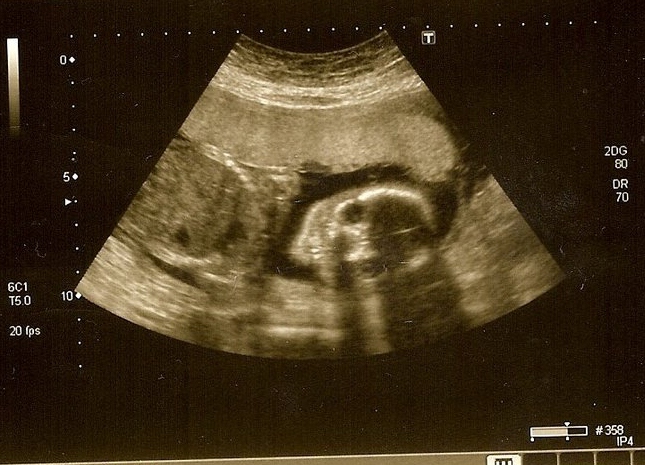

It was good to sit down with my hubby and a glass of pink and fizzy, that birthday evening and recall how we felt when he was born. Even before that: the OMG moment when I realised that my supposed UTI was in fact a pregnancy. How the anaesthetist and I were discussing how to get on to Countdown while I was having my c-section and the first time I got to hold that funny looking bundle of baby boy. We talked about autism: our disappointment with professionals, frustrations with friends who can’t accept or try to understand how Pwd’s condition affects him and us. We have never felt disappointed in him. Oh yes, he can be a frustratingly, infuriatingly stubborn character then so is someone else I know (guess who). I knew my child wasn’t typical from the start and I think having that realisation so early is a big boost to acceptance. Your happy hormones are flowing and you meet the child you’re going to love until your dying day.